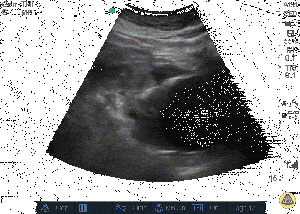

[[File:Ruptured_AAA_Tanguay.gif|thumbnail|Ruptured AAA<ref>http://www.thepocusatlas.com/aorta-1/</ref>]] | |||

Abdominal Aortic Aneurysm

Aortic Dissection

- In the setting of ruptured AAA, blood may not show up in a fast exam if the bleeding is retroperitoneal

- AAA vs Dissection

- Dissections will continue while AAA typically are located in single area

- Dissections can be a normal diameter

- Utrasound generally cannot differentiate ruptured from an intact AAA. The distinction is made based on clinical context.